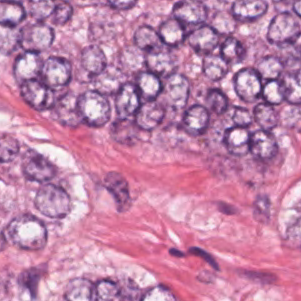

As an essential part of digital pathology, histopathology image analysis is playing increasingly important role in cancer diagnosis, which can provide direct and reliable evidence to diagnose the grade and type of cancer. This paper deals with nuclei segmentation, an important step in histopathological image analysis. The purpose of nuclei semgentation is not only counting the number of nuclei but also obtaining the detailed information of each nucleus. So unlike nuclei detection, here the outputs are the contour of each nucleus instead of only the position of their central points. Hence we can exactly extract each nucleus from the image and make it available for further analysis. For example, the features of the individual nucleus and the distribution of nuclei clusters can be used to grade and classify status of breast cancers [3, 4]. Because of appearance variation such as color, shape, and texture, nuclei segmentation from histopathological images could be very challenging, as illustrated in Fig.1, in which it is very challenging even for human to recognize and segment all nuclei within the images. Fig.1(a) and Fig.1(b) illustrate two histopathological images from different organs. Fig.1(c) and Fig.1(d) are two histopathological images from same organ but have different cancer grade.

H&E stain is the most widely used stain protocol in medical diagnosis. Typically, the nuclei of cells are stained to blue by Haematoxylin while cytoplasm is colored to pink by Eosin. But in practice, the color of H&E stained images could vary a lot due to variation in the H&E reagents, staining process, scanner and the specialist who performs the staining, as shown in Fig.1. A few H&E stain normalization methods[23, 24, 25] have been proposed to eliminate the negative interference caused by color variation. We tried two of them[23, 25] to normalize the raw H&E stained images. For our segmentation algorithm, we did not find any considerable difference between these two normalization methods. Particularly, the result shown in experiment section III is generated based on the images normalized by the method in [23]. Given a target image, this method is able to convert one image’s color into the target image’s color space based on sparse non-negative matrix factorization(NMF). We choose one best stained H&E image as the target and convert other images into its color space. According to the recommendation in [23], the hyper-parameter should be set between 0.01 and 0.1. In our experiment, is set to 0.1.

Figure 6 shows how our method segments the nuclei step by step. The color variety is well controlled by the color normalization procedure. The prediction result shows clear nuclear areas and nucleus boundaries. In the final segmentation result and ground truth image, each nucleus is represented by a different color.